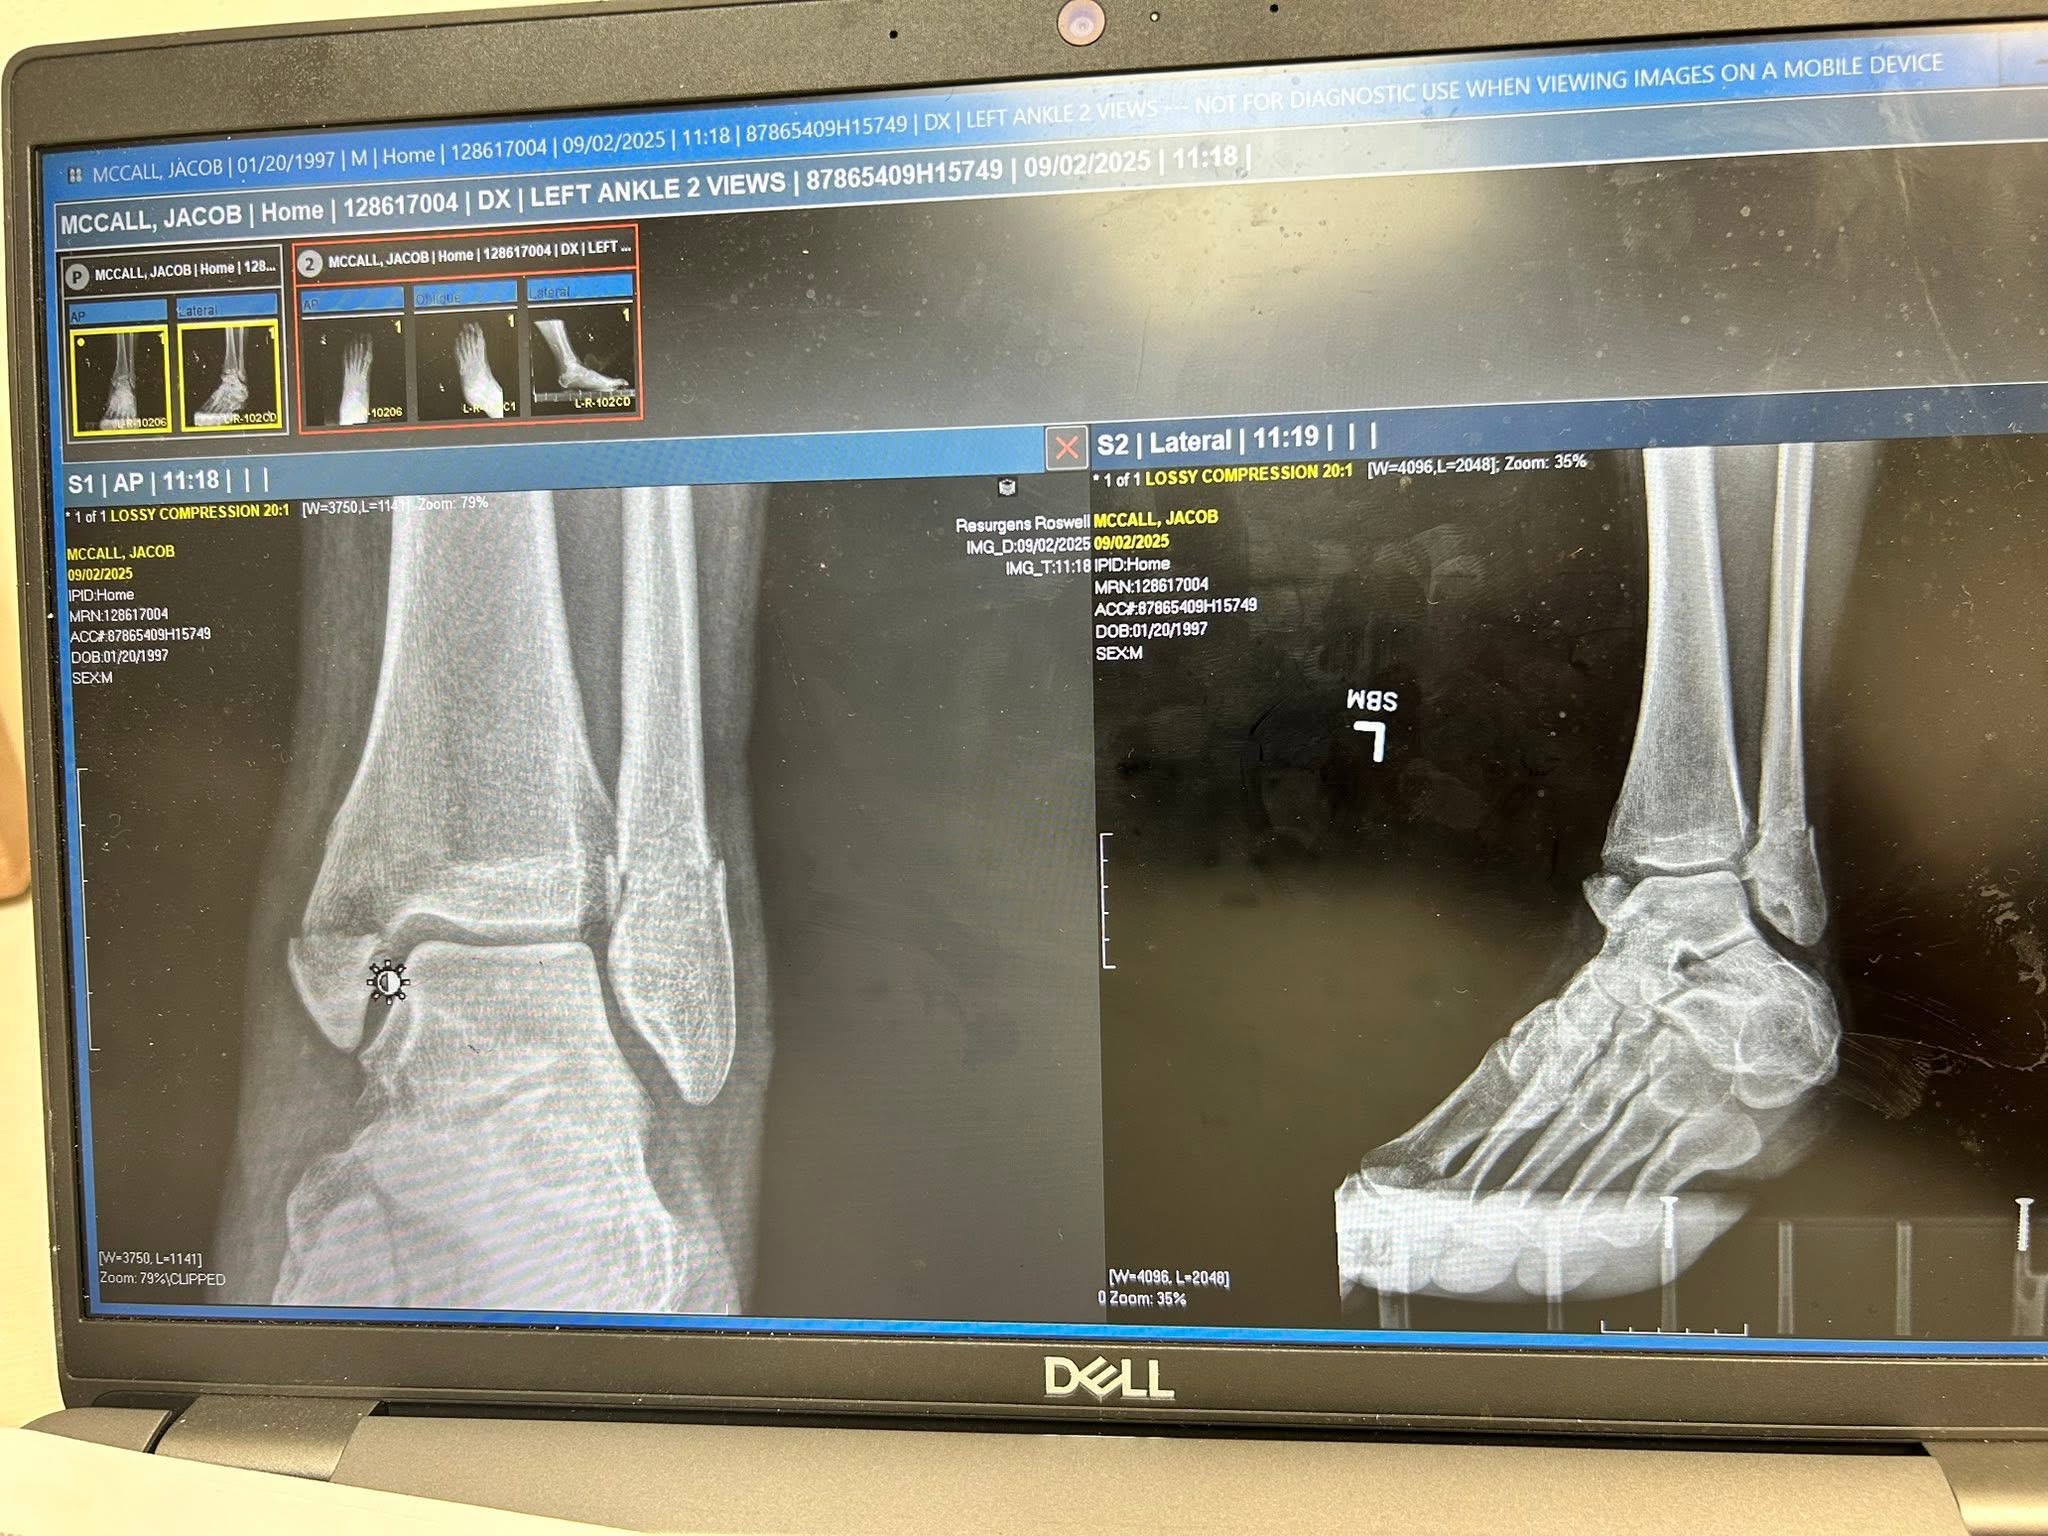

While his bike came out with only minor damage, Jacob wasn’t as fortunate: his tibia and fibula were both severely fractured. He now faces major surgery requiring hardware, followed by months of rehabilitation. At minimum, his racing season is over—and the medical expenses he is facing will easily reach into six figures.